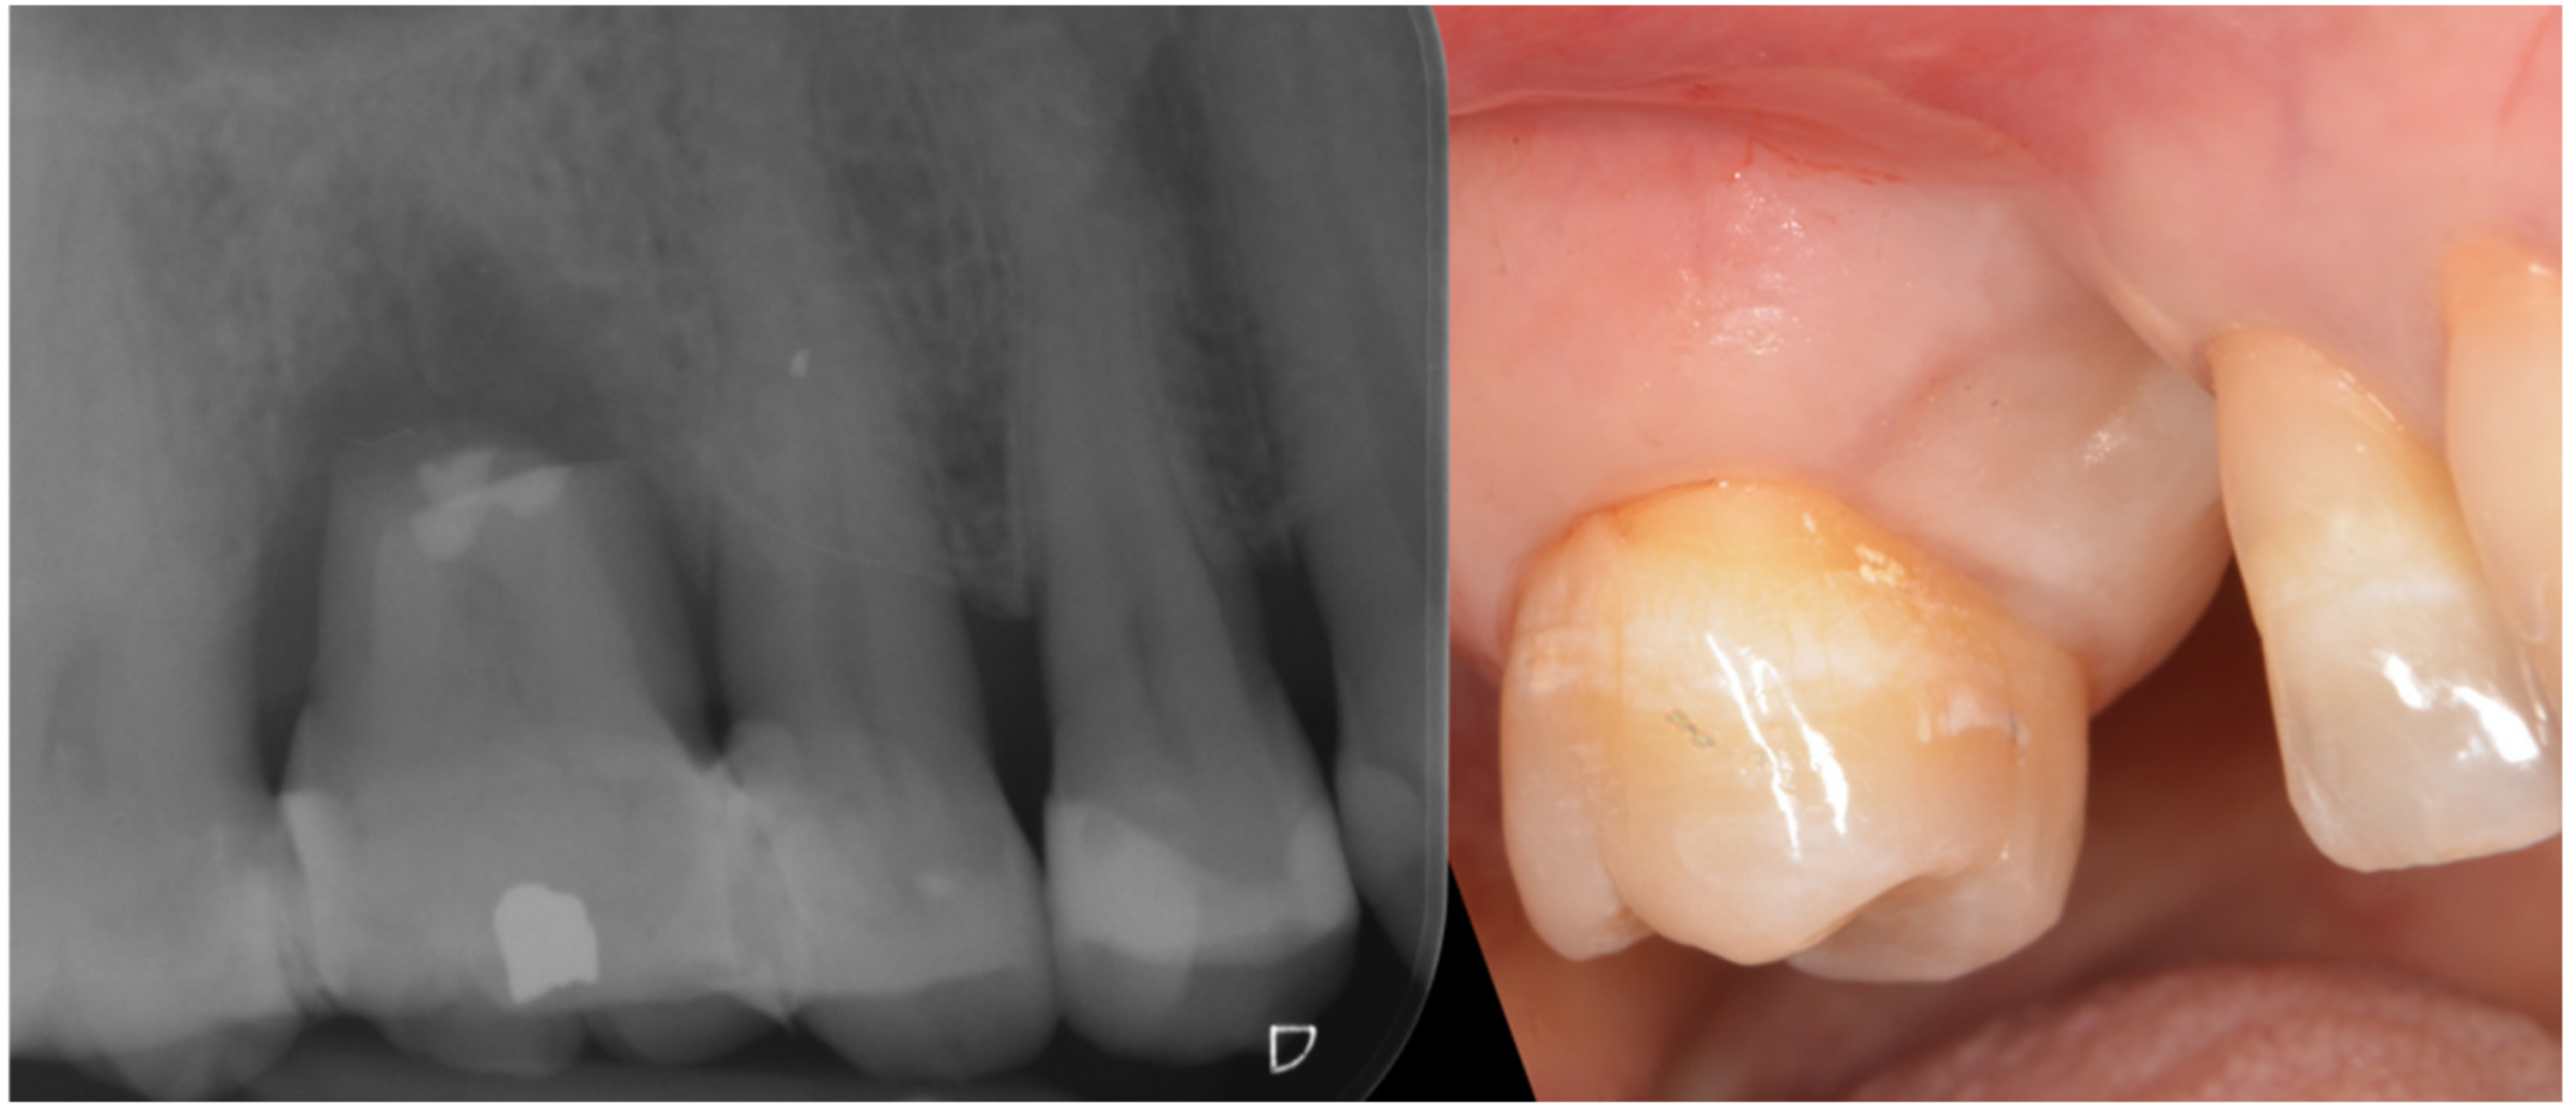

Three months after implant surgery the fixture was restored with a ceramic crown and a radiograph taken 5 years after augmentation. Figure 4 not only shows the perfect maintenance of the osseointegration after loading, but also how the GTR effect is visible on the mesial of tooth 26 with an attachment gain of 6 mm; the probing (PPD) at the time of recall was 3 mm The tooth remained in function and the patient can clean the area well with interproximal tooth brushes and dental floss.

Figure 4.

Rx taken at a 5 year follow-up showing the stability of the regeneration on both implant and tooth side.